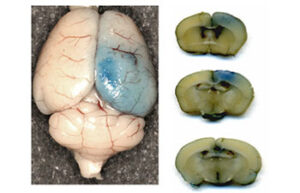

- Evaluation of brain Evans blue staining test in rats and mice